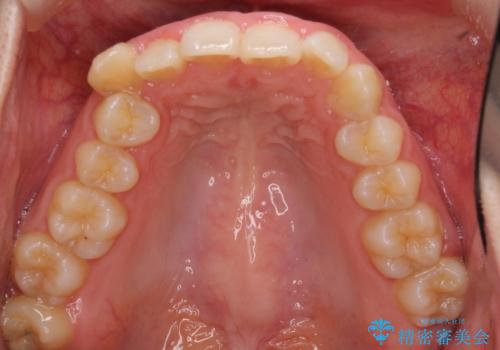

- 八重歯を気にして来院された患者様です。

八重歯の後ろの歯を1歯抜歯し、補助装置(リンガルアーチ)を用いて八重歯の位置を改善し、その後インビザラインにより矯正治療を行うこととしました。

下顎前歯が1本欠損したスリーインサイザーという状態であるため、上下の前歯の咬み込みが深くなったり、奥歯の咬み合わせが理想的なものとならなかったりという仕上がりになってしまいます。

前歯の見た目や奥歯の咬み合わせに、患者様が違和感を感じない状態として治療を終えました。